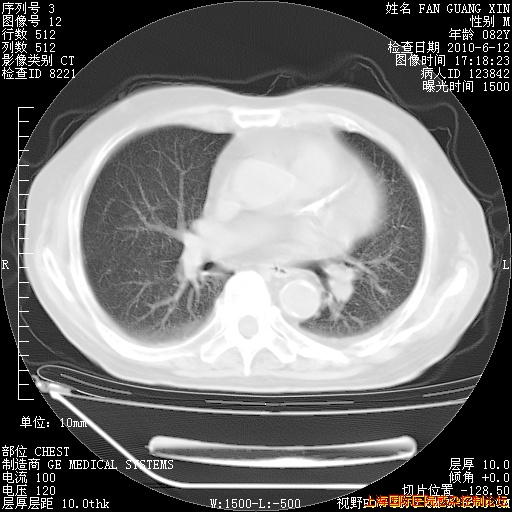

补发6月12日肺部CT肺窗

6月12日肺窗

6月12日纵膈窗